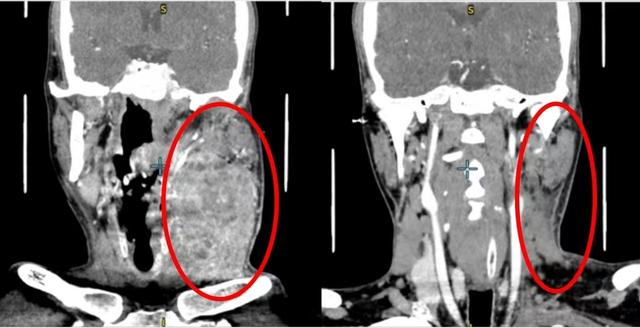

这名33岁患者的影像检查线上,肿瘤病灶从舌头转移到了颈部。

“从临床经验来看,舌癌高发人群以五六十岁中老年人居多,年轻人一般较少,但一旦年轻人发现舌癌,往往进展就很快。”首次接诊这名患者的口腔颌面-头颈肿瘤科主任医师胡永杰在接受澎湃新闻记者采访时表示,从患者发现自己舌头左侧有溃疡,到来上海第九人民医院看病,前后才2个多月,“我们看到病人来门诊时,口腔溃疡不但没有愈合,反而迅速发展,蔓延到了整个舌头再到下颌,不仅舌头动不了,嘴巴也张不开,吃东西也困难。不仅如此,肿瘤病灶还从舌头转移到了颈部,直接包住了左侧颈动脉,属于晚期高危病人。”

多学科专家会诊后透露,这名患者因肿瘤太大,同时已经发展颈部转移累及到了颈动脉,如果直接手术切除肿瘤,会有死亡风险。为降低手术风险,经评估,专家们决定对这名患者采用个体化治疗:先药物治疗缩小肿瘤,再进行根治性手术,后续再进行靶向治疗、免疫治疗和化疗等联合治疗。